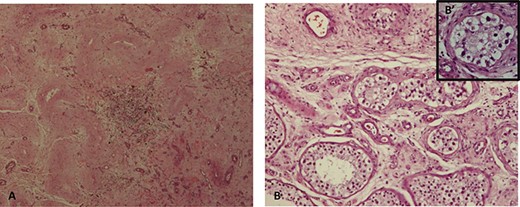

The patient was admitted for a radical right orchidectomy. Gross examination revealed a 5 × 4-mm, well-demarcated solitary, whitish scar, with focus of mononucleated inflammatory cells, siderophages, hyalinized tubules and increased vascularity on light microscope. At scar periphery, there was a germ cell neoplasia in situ (Fig. 4).

(A) fibrous scar with focus of lymphoplasmacytic inflammatory cells and hyalinized ghost seminiferous tubules; (B) sclerotic and atrophic seminiferous tubules peripheral to the scar (H&E 10×), (B′) some with germ cell neoplasia in situ (H&E 40×).